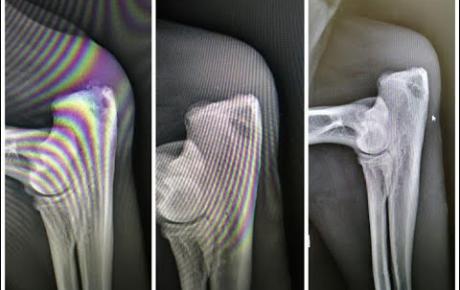

X-Ray Examination

Presence of mineralisation at the back of the left elbow olecranon tuber.

Ultrasound diagnosis: III degree muscle lesion to the left triceps brachii muscle.